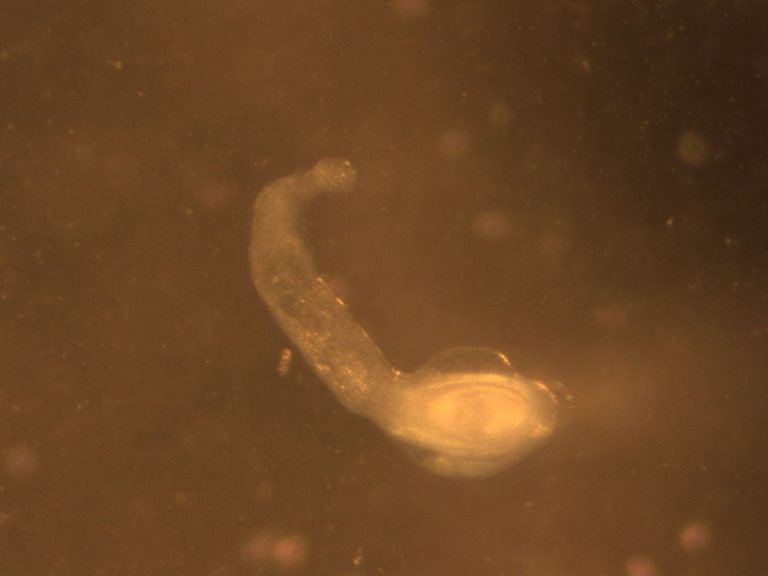

حقوق الصورة: موقع wormtherpy.com